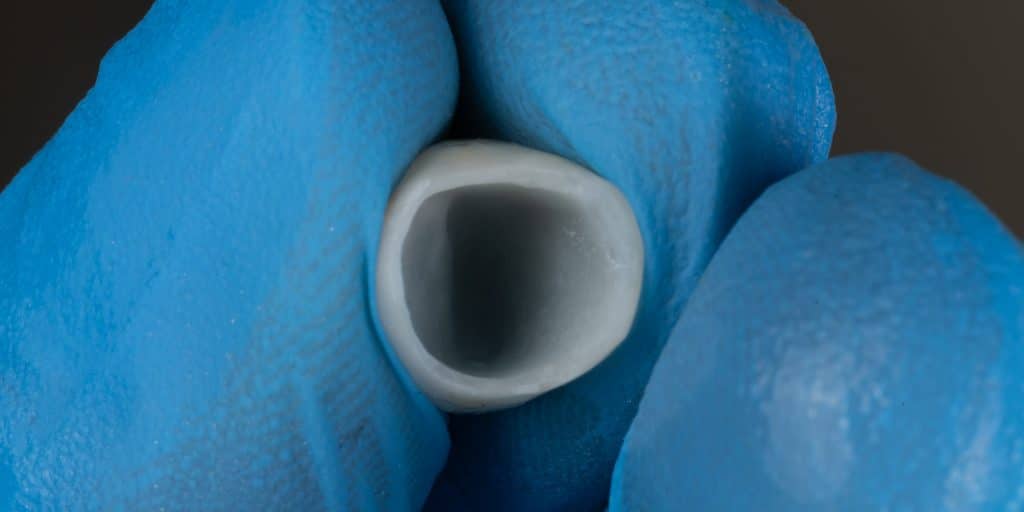

Final Prep + Composite filling for the other central

Zoomed in

E-max crown